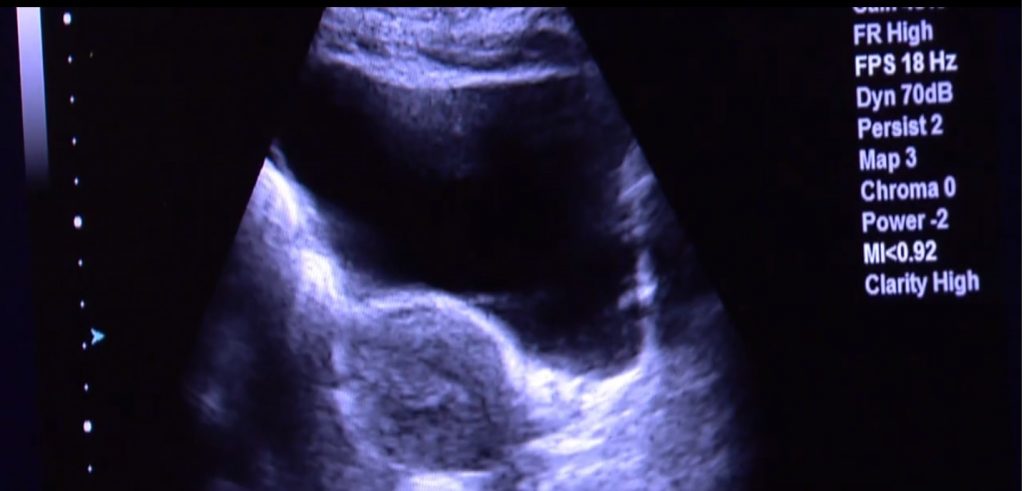

Essa foi a primeira vez no mundo em que um caso assim aconteceu. O útero tinha sido transplantado em setembro de 2016 de uma mulher que teve morte cerebral para essa paciente. O procedimento durou 10 horas (os médicos religaram as veias e artérias, assim como a saída do útero para a vagina) e ocorreu no Hospital das Clínicas, da faculdade de medicina da USP – Universidade de São Paulo. E foi la mesmo que o bebê da paciente veio ao mundo, no dia 15 desse mês.